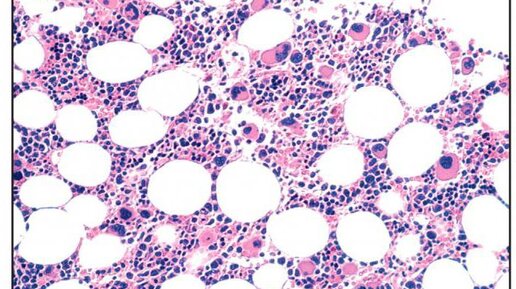

Агранулоцитоз – это клинико-гематологический синдром, в основе которого лежит резкое уменьшение или отсутствие нейтрофильных гранулоцитов среди клеточных элементов периферической крови. Агранулоцитоз сопровождается развитием инфекционных процессов, ангины, язвенного стоматита, пневмонии, геморрагических проявлений. Из осложнений часты сепсис, гепатит, медиастинит, перитонит. Первостепенное значение для диагностики агранулоцитоза имеет исследование гемограммы, пунктата костного мозга, обнаружение антинейтрофильных антител...

Напоминаем о важности здоровья. Что такие нейтрофилы? Нейтрофилы — важные клетки иммунитета, способные атаковать бактерии, которые попали в ваш организм. Название их идет от способности менять цвет при микроскопии кислыми и щелочными красителями. Наш костный мозг образует данные клетки. После чего они оказываются в кровотоке и перебираются в область инфекции, где нейтрализуют бактерии-нарушителей. Именно нейтрофилы оказываются в очаге воспаления первыми и сразу же начинают выстраивать защитные реакции, буквально за считанные секунды...